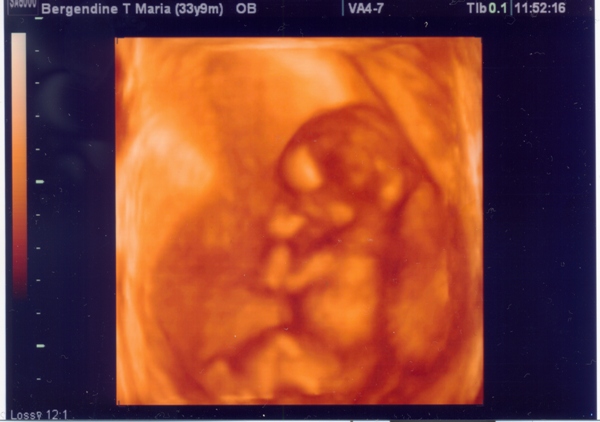

Amúgy mutatok nektek egy sztárfotót a mi kis Fiúnkról(?)

Egyelőre csak 60%-ban biztos a neme, majd kiderül! :wink:

Kép

Ez a 14-ik héten készült.